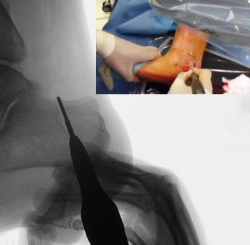

Figura 6. Imagen fluoroscópica del trazo plantar de la osteotomía y su correspondencia en cirugía.

Se comprueba si la osteotomía es completa; si es así, la tuberosidad del calcáneo podrá manipularse hacia lateral y medial. Si no se consigue mover, será necesario repasar la osteotomía con la fresa palpando y fresando las posibles zonas no osteotomizadas que queden.